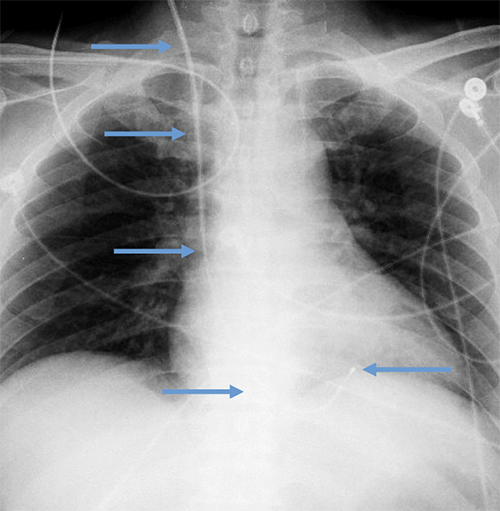

- CEID images with lead types:

Pacemaker with transvenous leads

Pacemaker with epicardial leads

Defibrillator lead

Subcutaneous defibrillator

Cut epicardial wires (often hard to see)

Abandoned leads

Abanded leads plus generator

Temporary transvenous lead

Leadless pacemaker